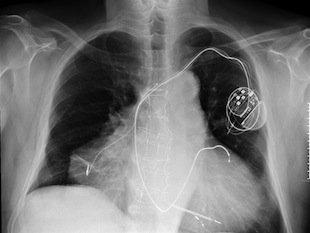

Երկու սիրտ ունեցող տղամարդը

Իտալիայում տարիներ առաջ ծնվել էր մի մարդ, ով երկու սիրտ ուներ։ 2010 թվականին նրա մոտ սրտի կրկնակի կաթված էր գրանցվել, սակայն նա փրկվել էր։ Մարդիկ կատակում էին, թե այսուհետ պետք է բոլոր մարդկանց սրտի հավելյալ փոխպատվաստում անել, որպեսզի բոլորը երկու սիրտ ունենան և կաթվածից չմահանան։